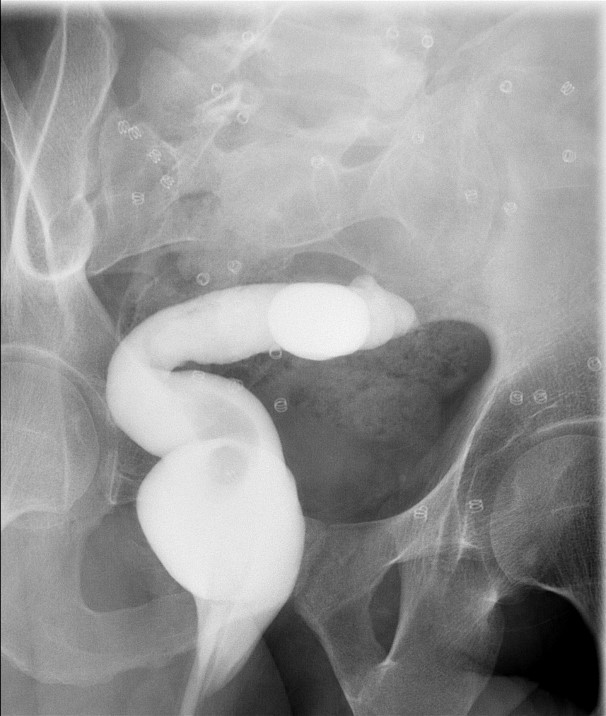

- Ileoanal J Pouch

- The iloeanal J pouch is created when patients have a total proctocolectomy.

- During this exam, you will focus on the bowel in the pelvis.

- When reviewing the preliminary scout film, you should see multiple surgical chain sutures in the pelvis

(key image 31)

(key image 32).

- After the enema tip has been placed but before contrast material has been administered, obtain a fluoroscopic spot film of the rectum with the patient in the left lateral position

(key image 33).

- As you instill contrast material into the J pouch, obtain images of the pouch and ileoanal anastomosis fully distended with contrast material in each of the following four (4) positions:

- left lateral

(key image 34)

- left posterior oblique

(key image 35)

- supine (AP)

(key image 36)

- right posterior oblique

(key image 37).

- Contrast material may be seen filling the ostomy bag (if present) before all images have been obtained. If this happens, proceed to take the needed images, adjusting the postion of the ostomy bag if needed.